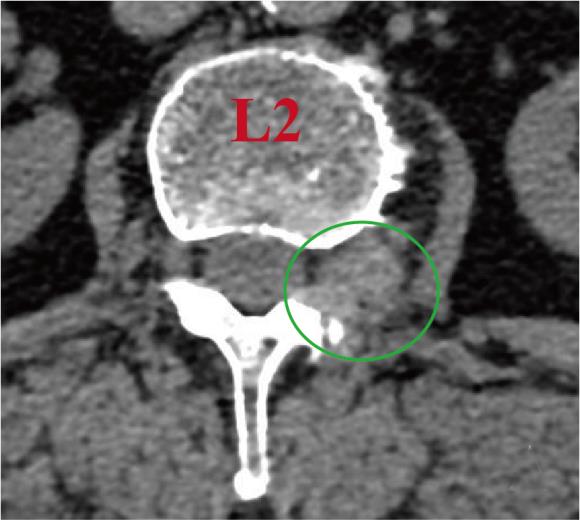

摘要:目的 观察单通道非同轴脊柱内镜经椎间孔外入路(椎板外切迹)治疗极外侧椎间盘突出症(FLLDH)的临床疗效。方法 回顾性分析2022年5月-2024年5月该院收治的,行单通道非同轴脊柱内镜经椎间孔外入路(椎板外切迹)治疗的FLLDH患者70例。于术前和术后,评估腰腿疼痛程度、腰椎功能和临床疗效。结果 相较于术前,术后3 d和3个月,患者下肢视觉模拟评分法(VAS)评分、腰部VAS评分、Oswestry功能障碍指数(ODI)、数字分级评分法(NRS)评分和Roland-Morris功能障碍问卷(RMDQ)评分明显降低,日本骨科协会(JOA)评分明显升高,差异均有统计学意义(P < 0.05);改良MacNab评分标准显示,末次随访时的优良率为94.28%。结论 单通道非同轴脊柱内镜经椎间孔外入路(椎板外切迹)治疗FLLDH,能明显改善患者腰腿疼痛和腰椎下肢功能,其具有创伤小、易操作、安全性高和疗效好等优点,值得在临床推广应用。